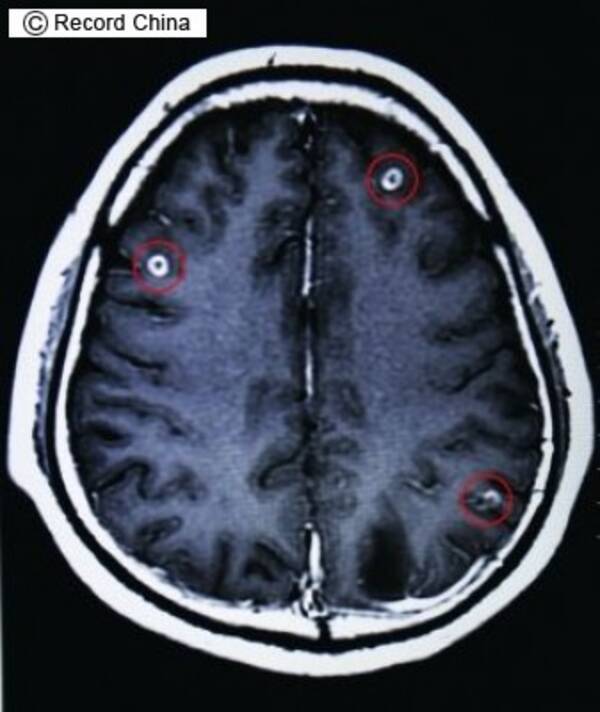

脳 寄生 虫